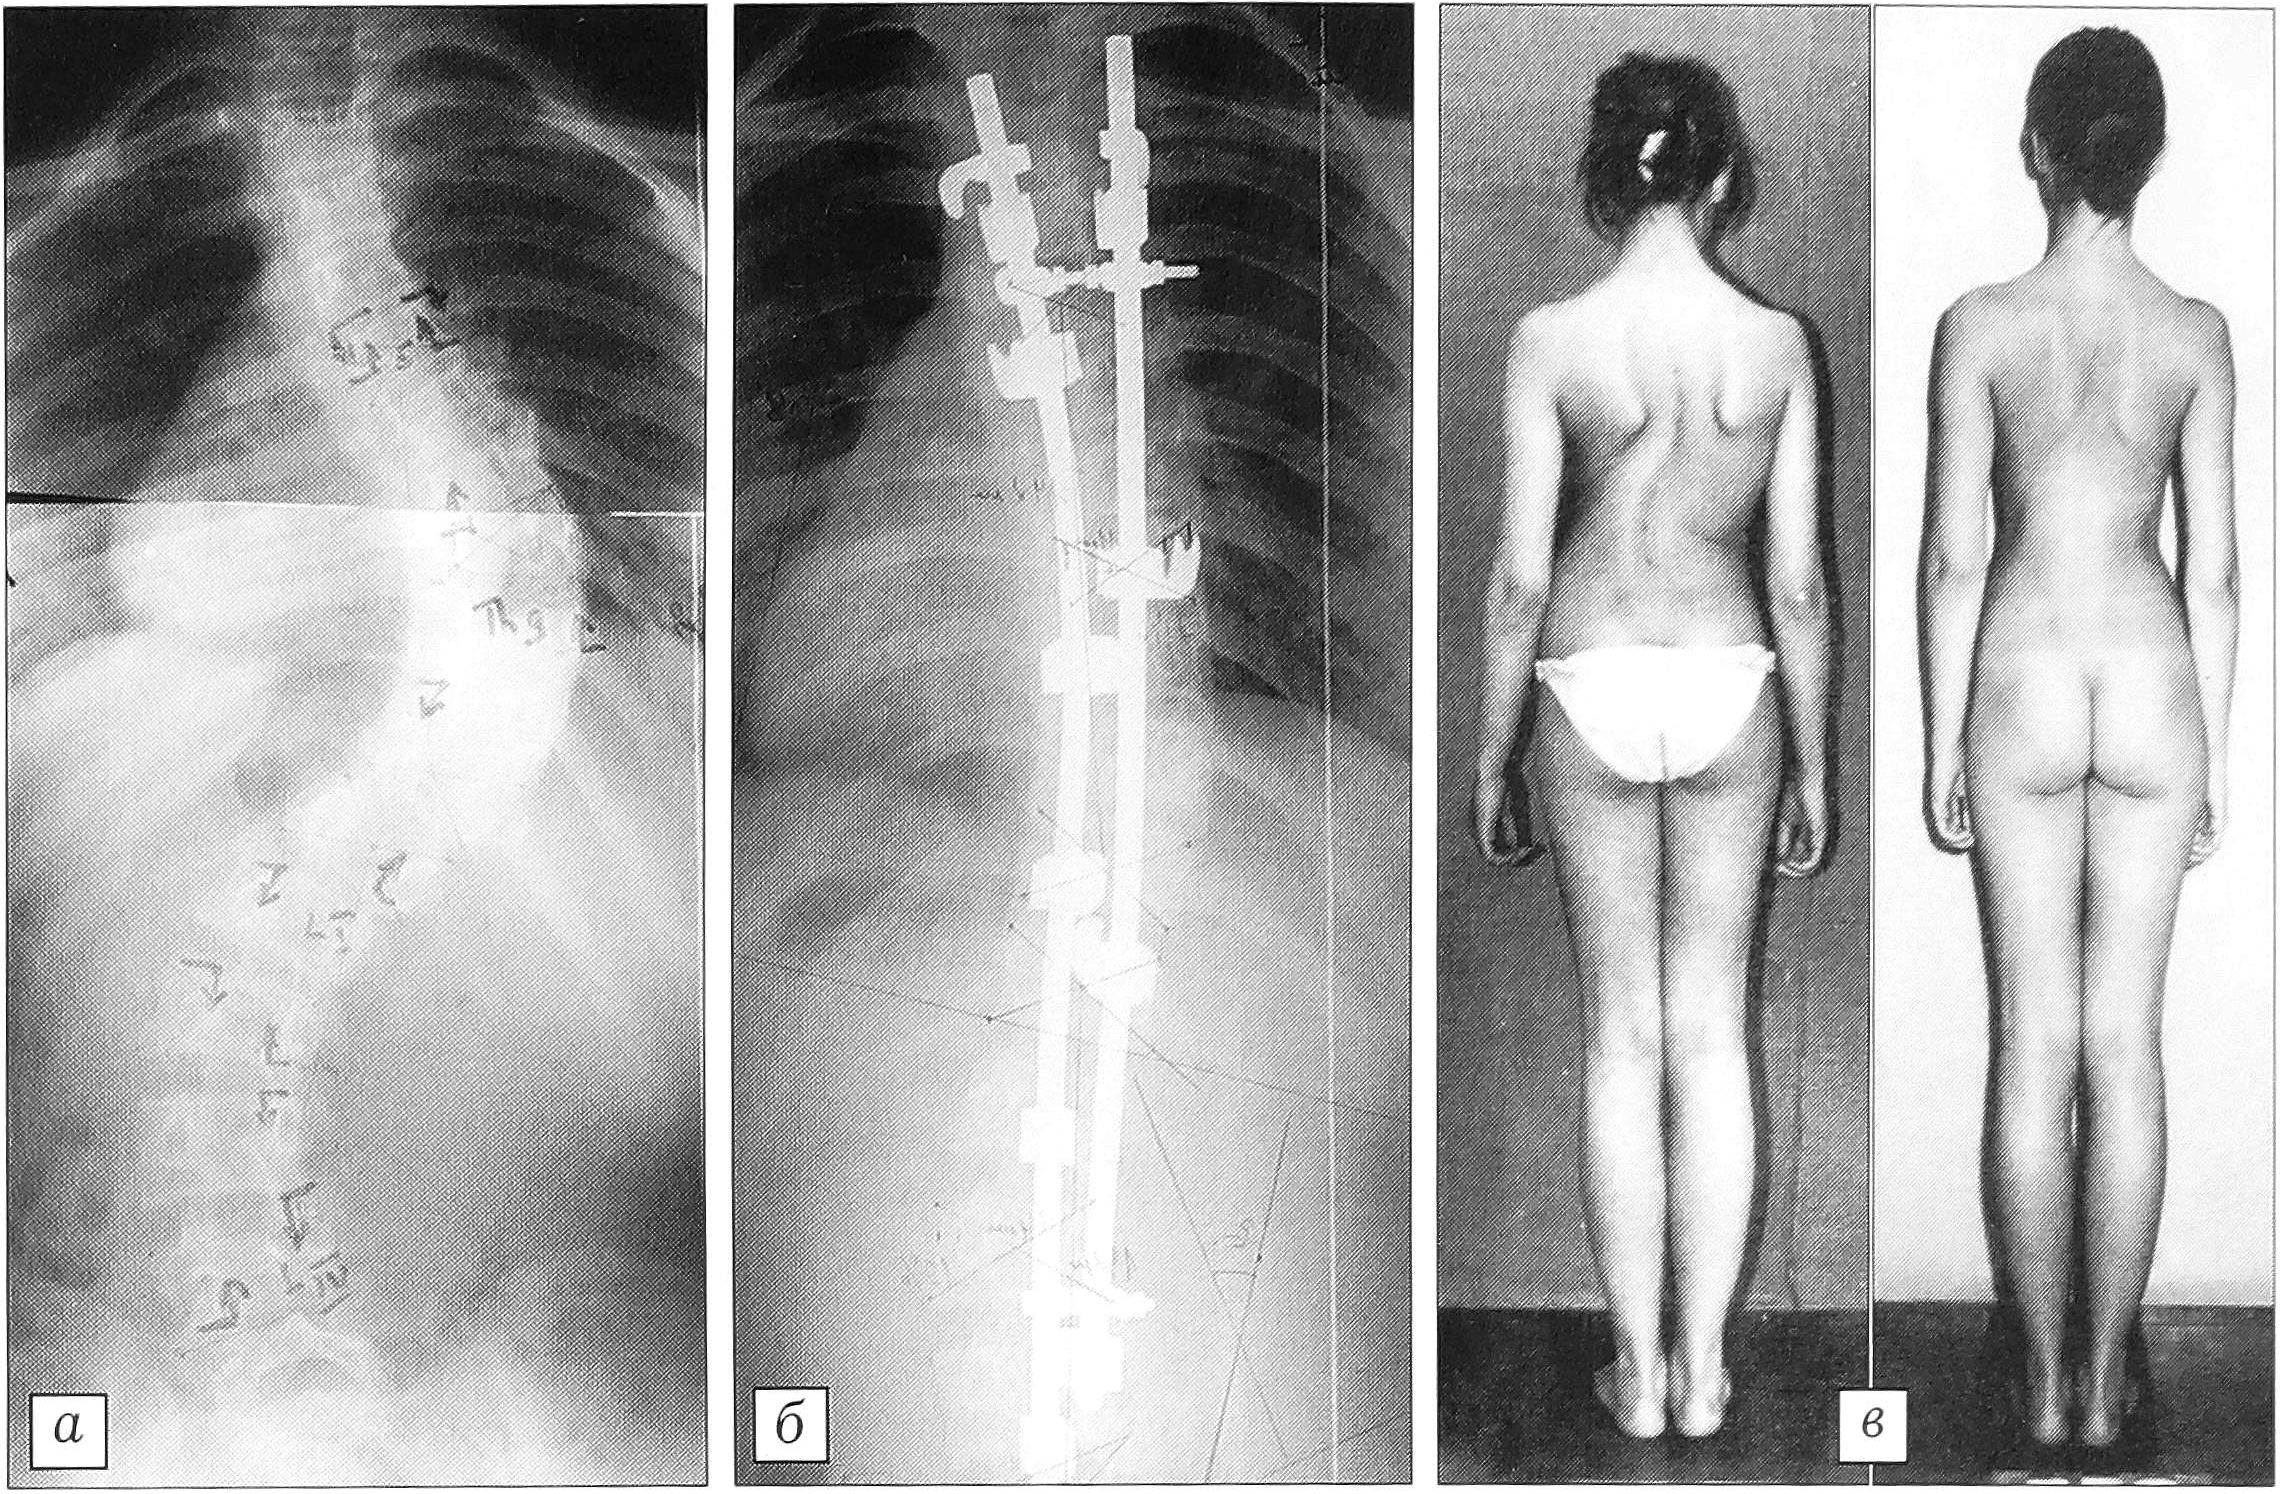

При деформациях от 75 до 90° «деротирующий маневр» обычно невыполним из-за ригидности позвоночника и выраженной торсии. В таких случаях с успехом используется трехстержневая техника [10] (рис. 5).

Рис. 5. Больная Г-ва 16 лет (подростковый сколиоз). Коррекция первичной дуги в результате двухэтапного вмешательства с использованием трехстержневой техники со 105° (а) до 54° (б). Срок наблюдения 3 года (в), потеря коррекции 2°.